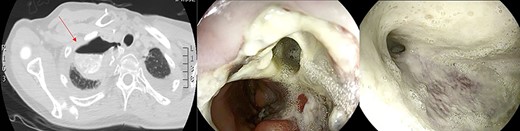

After the 14th session, the endoscopic evaluation showed a significantly cleaner and smaller cavity (1 cm). Two esophageal fully covered SEMS (Taewoong Niti-S Beta Stent) allowed the patient to have a liquid diet while the leak was safely healing: the stents were subsequently placed and kept for 3 weeks each. Endoscopy and esophagram were performed after SEMS removal, and they demonstrated leak resolution, with a tiny persistent depression at the site (Fig. 4). The patient has not had symptoms of recurrent fistula formation for over 6 months.